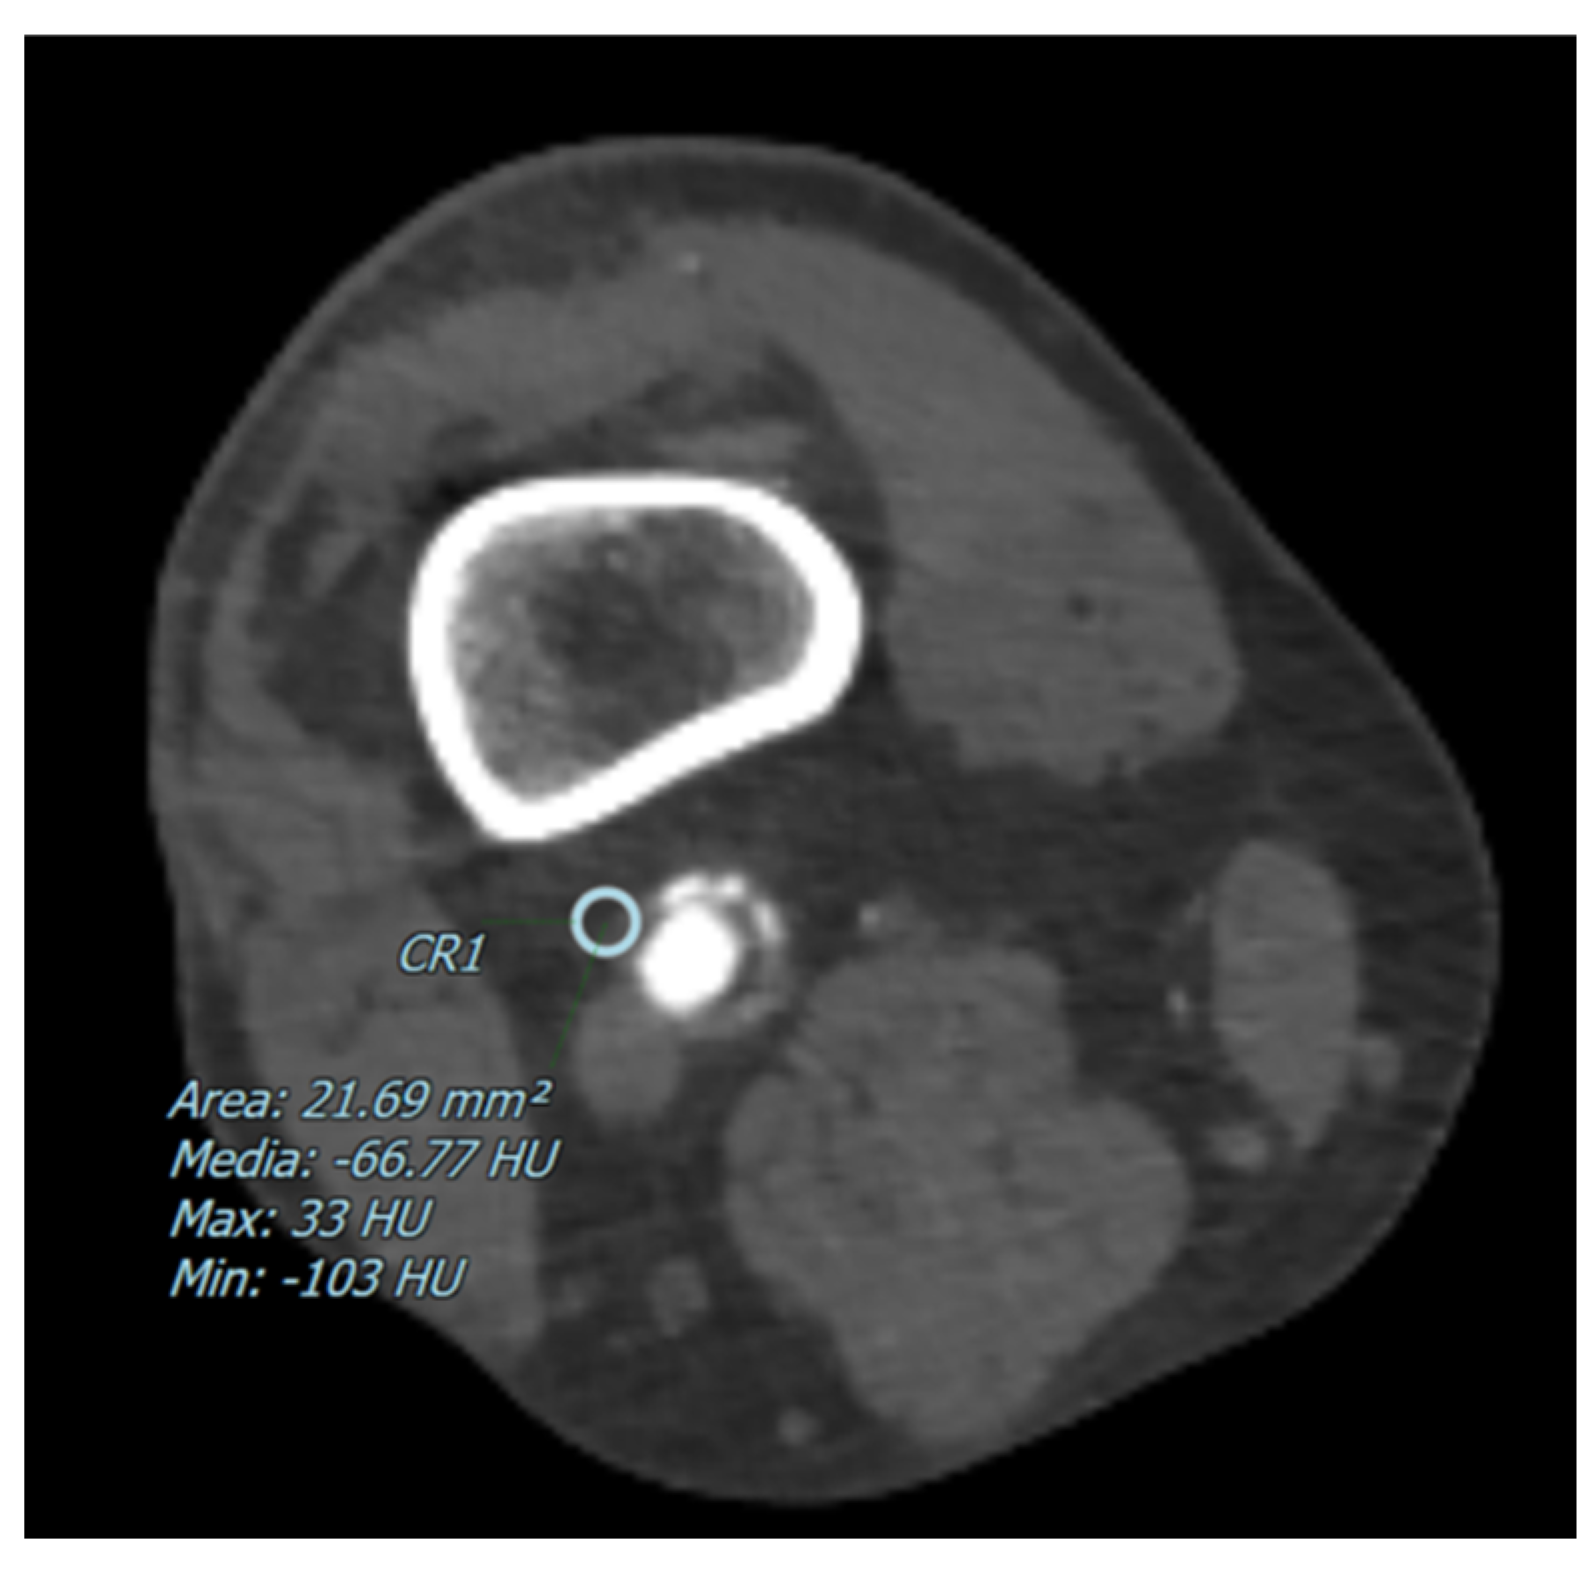

The degree of arterial stenosis was categorized into four distinct classes: <25%, 25–50%, 50–70%, and >70%. Perivascular adipose tissue (PVAT) density, measured in Hounsfield Units (HU), was determined by positioning a 5 mm circular region of interest (ROI) adjacent to the vascular wall, as shown in Figure 1 and Figure 2. Additionally, for each of these vascular segments, both the degree of stenosis and the corresponding PVAT attenuation values were quantitatively assessed.

Figure 2.

The figure shows an example of a CT image with a pointed perivascular adipose tissue density in a patient with a preserved artery canalization The blue circle represents the ROI where the perivascular adipose tissue density has been measured in Hounsfield Units (HU).